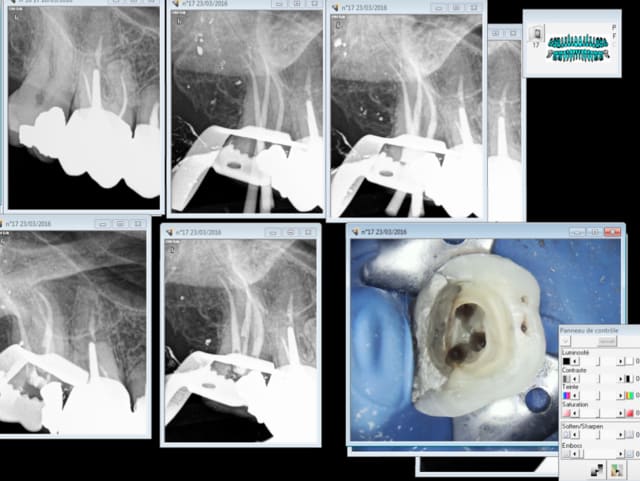

Pour éviter ce genre de carnage utiliser une fraise endo pour ouvrir la chambre, ouvrir les entrées canalaires au largo sur double bague verte, pas forcer sur les instruments d'endo, ne pas hésiter à récapituler ( 4 fois s1- r25 dans ce cas) , radio cone en place, radio cone scellé, radio cone condensé. -)

Ici j'ai trouvé les entrées canalaires au SX. Evasées au largo puis sx largo un peu plus loin ( 3- 4 mm ) et sx. Ensuite le S1 a Commencé à forcer à 18 mm environ et je suis passé au R 25 jusqu' à 18 mm. le s1 a progressé jusqu'à 20 mm puis recommencé à forcer et je suis passé au R 25 à 20 mm. le S1 a ensuite progressé à 22 mm de lt longueur à laquelle l'endo master a trouvé la LT.

J'ai ensuite passé le R 25 à 22 mm.

Je brosse les parois avec le R 25. Ca adoucit la courbure et permet au S1 de progresser. Aucun cathétérisme manuel.